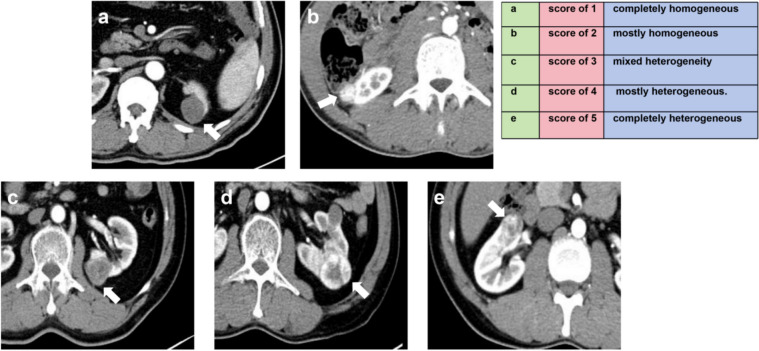

Methods: A retrospective collection of 331 patients with pathologically confirmed renal masses were enrolled in this study. Two radiologists independently assessed the CT images: in addition to heterogeneity score (HS) and mass-to-cortex corticomedullary attenuation ratio (MCAR), measured parameters included ratio of major diameter to minor diameter at the maximum axial section (Major axis / Minor axis), tumor-renal interface, standardized heterogeneity ratio (SHR), and standardized nephrographic reduction rate (SNRR). Spearman's correlation analysis was performed to evaluate the relationship between SHR and HS. Univariate and multivariate logistic regression analyses were employed to identify independent risk factors and then CT-score was adjusted by those indicators. The diagnostic efficacy of the modified CT-scores was evaluated using ROC curve analysis.

Results: The SHR and heterogeneity grade (HG) of mass were correlated positively with the HS (R = 0.749, 0.730, all P < 0.001). Logistic regression analysis determined that the Major axis / Minor axis (> 1.16), the tumor-renal interface (> 22.3 mm), and the SNRR (> 0.16) as additional independent risk factors to combine with HS and MCAR. Compared to the original CT-score, the two CT algorithms combined tumor-renal interface and SNRR showed significantly improved diagnostic efficacy for ccRCC (AUC: 0.770 vs. 0.861 and 0.862, all P < 0.001). The inter-observer agreement for HG was higher than that for HS (weighted Kappa coefficient: 0.797 vs. 0.722). The consistency of modified CT-score was also superior to original CT-score (weighted Kappa coefficient: 0.935 vs. 0.878).